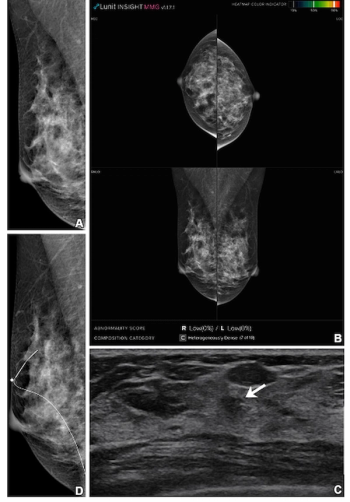

External validation testing revealed a deep learning combination of breast MRI, ultrasound and clinical factors had a 10 percent higher AUC for predicting axillary lymph node metastasis than sole use of MRI- or ultrasound-based deep learning models in patients with breast cancer.